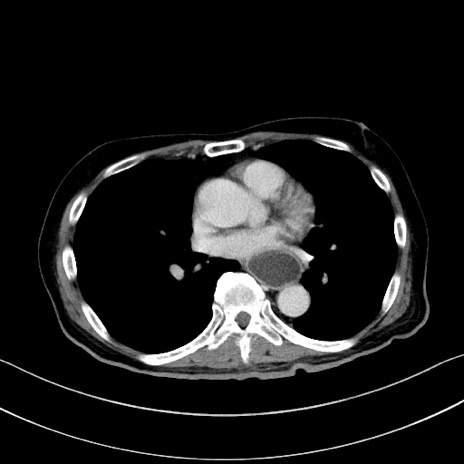

症例28(横断像)

【症例】60歳代男性

【主訴】嘔吐

【現病歴】胃癌にて胃全摘後。食思不振が悪化し、夜中に嘔吐することがある。

【既往歴】胃癌、胃全摘、脾摘、胆摘後

【データ】WBC 5900、CRP 10.56